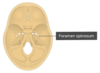

Foramen Magnum:Occupies central area of floor, transmits the medulla oblongata, the spinal portion of CNXI and the two vertebral arteries